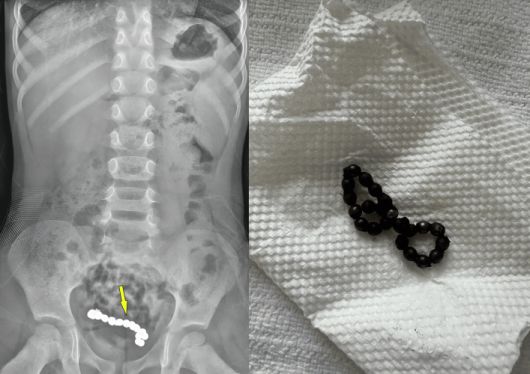

1년간 복통을 호소해 온 4세 남아의 뱃속에서 자석 조각 22개가 발견됐다. 큐레우스 캡처 |

복부 엑스레이(X-ray)와 컴퓨터단층촬영(CT) 결과, 하복부에서 사슬처럼 연결된 둥근 이물질 여러 개가 관찰됐다.

의료진은 복강경 수술을 진행했다. A 군의 배에서는 22개의 자석 조각이 나왔다. 자석들은 서로 붙어 있는 상태였다.

자석의 인력으로 A 군의 장 일부가 괴사해 장의 약 15㎝를 절제했다.